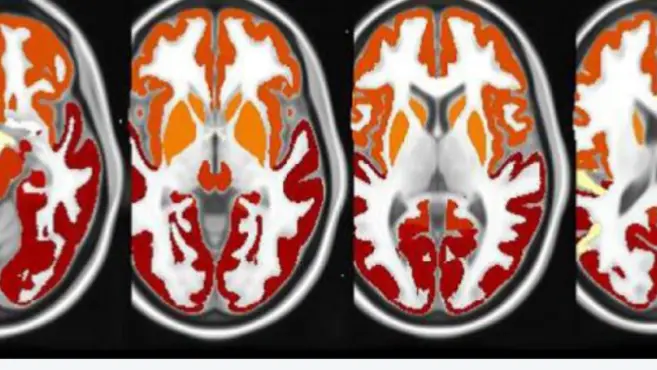

Using AI To Advance Imaging Operations & Analysis in Phase III Clinical Trials for Alzheimer’s

MIUA 2020: Transfer Learning for Brain Segmentation: Pre-task Selection and Data Limitations

Free Water Imaging in Alzheimer's Disease

Using AI to optimize Tau PET Imaging for Alzheimer’s Disease Clinical Development